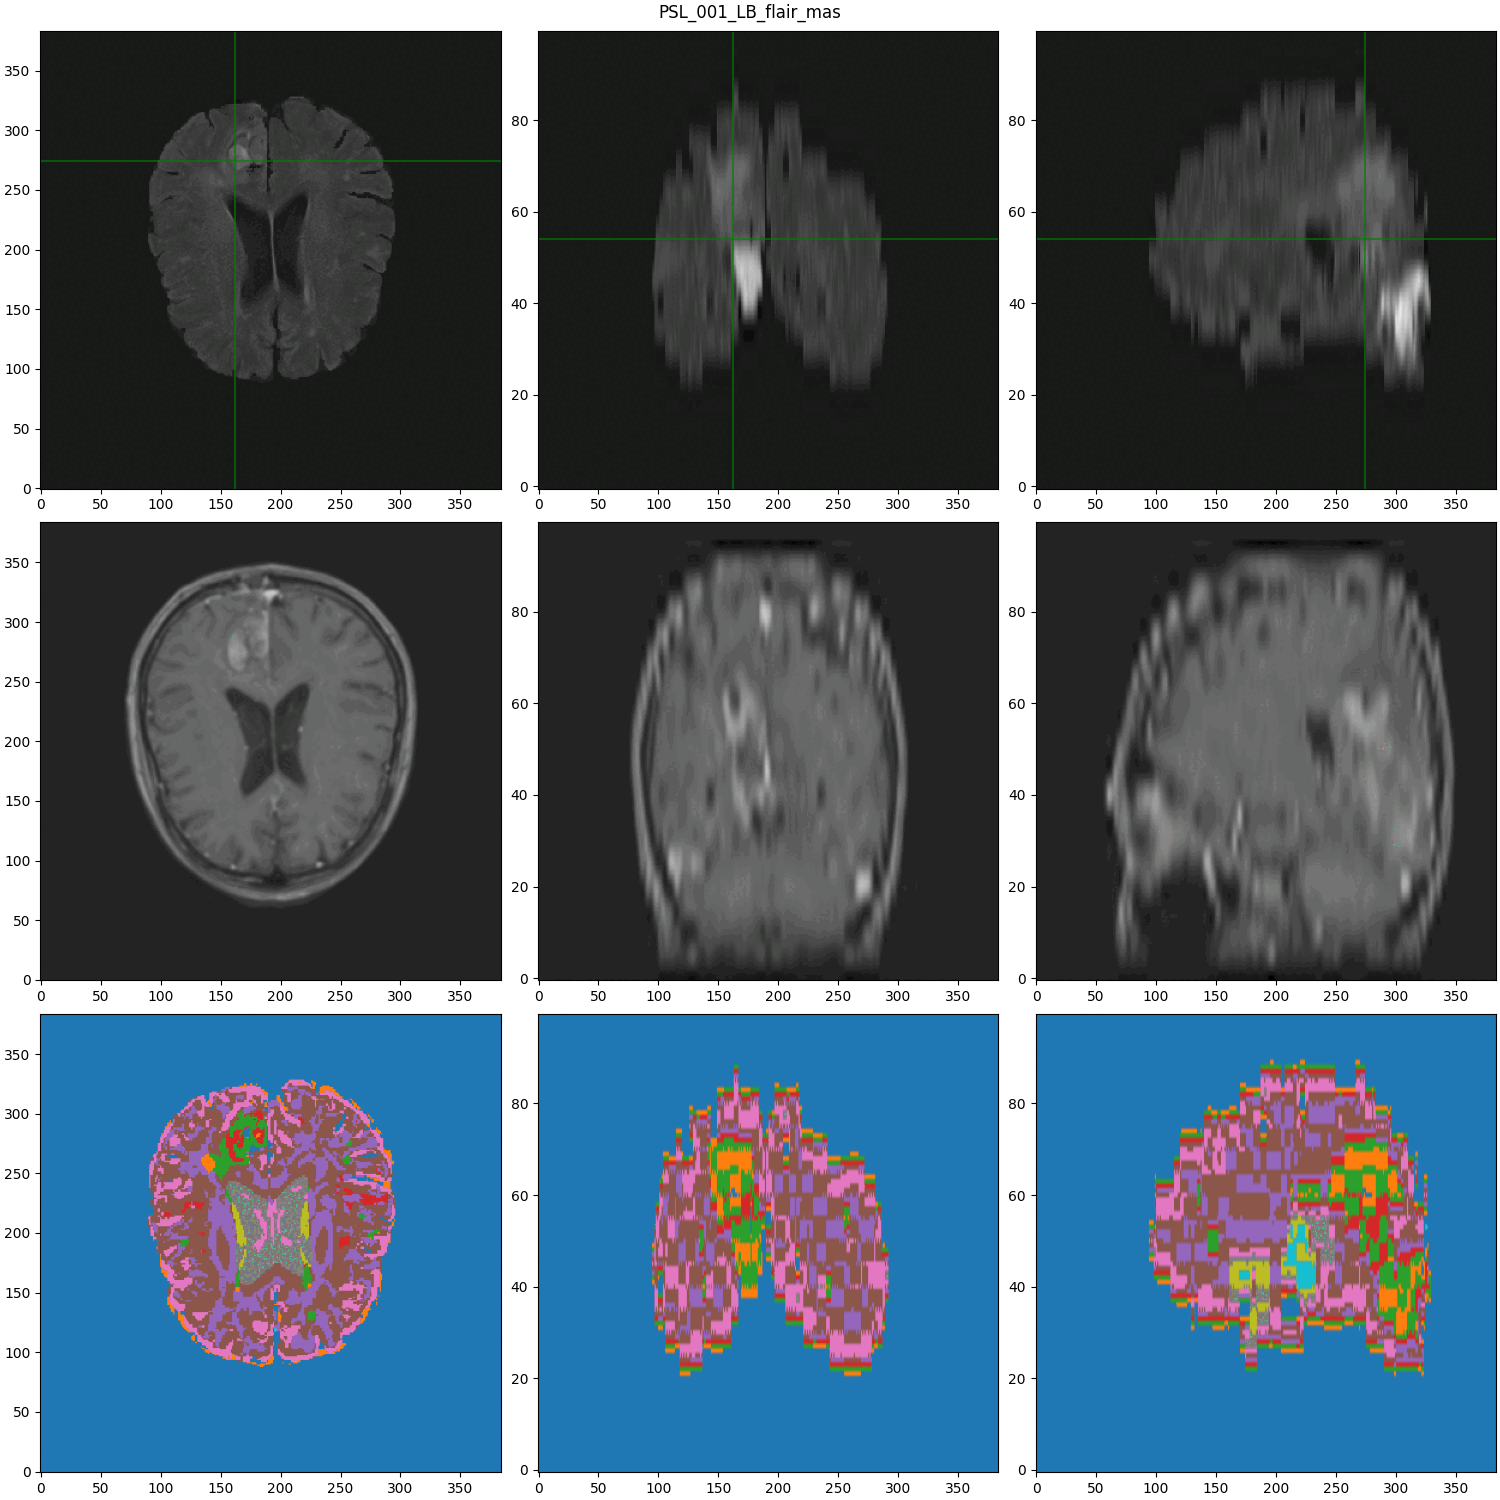

Data from :

segmented MRI

Data Nature

Rigid alignment

- Cancerous Growth (red - orange)

- White Matter Intensity reallocations (orange)

- Ventricule expansion (gray)

Registration difficulties